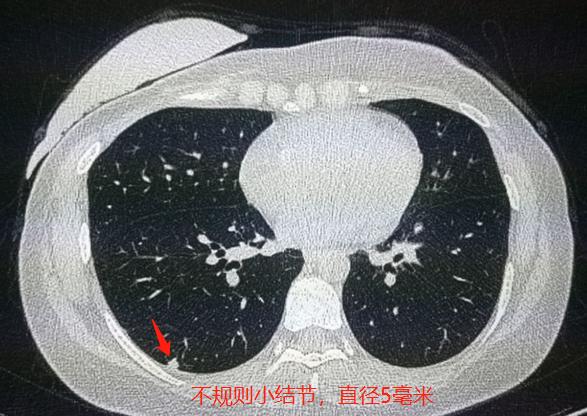

从片子上可以看到,右下肺胸膜下有一个不规则的实性小结节,直径4-5毫米。

又过了8个月,本次复查,就是上面第一张图片,小结节长到5毫米了。

《中国肺部结节分类、诊断与治疗指南(2016年版)》规定:直径<5mm的实性结节属于低危结节。处理策略:肺癌低危结节建议1年后随访,发现生长则纳入高危结节处理,无生长则继续行年度随访。

所以说,小岚这个结节虽然只有5毫米,但她有规范的随访对比,显示确切增大,应纳入高危结节,建议积极治疗。

并且她的肺结节位于胸膜下,很适合胸腔镜微创手术,解除隐患。

以上是我们建议她住院进一步诊治的依据。